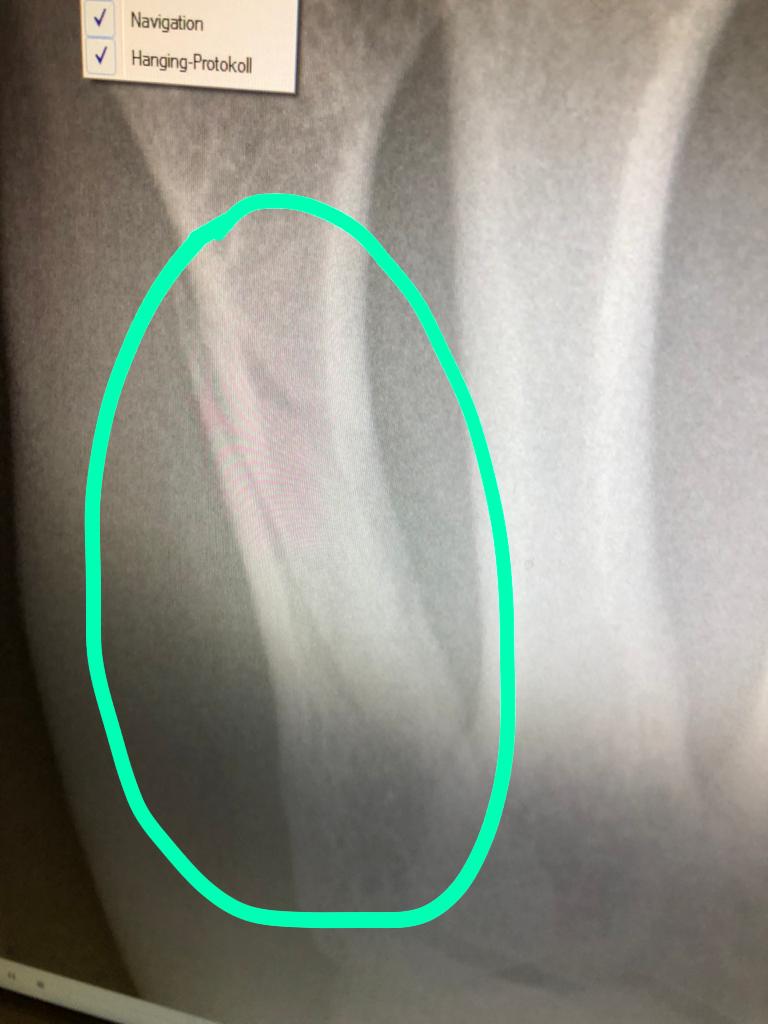

Спицов был доставлен в клинику доктора Doktor Johannes Huber from Kempten. По итогу осмотра и выполнения рентгенографии диагностирован перелом 5 пястной кости левой руки.